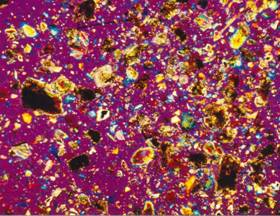

Weddellit a whewellit s příměsí

apatitu.

Zrnkový preparát, polarizační mikroskop, zvětšeno 160x